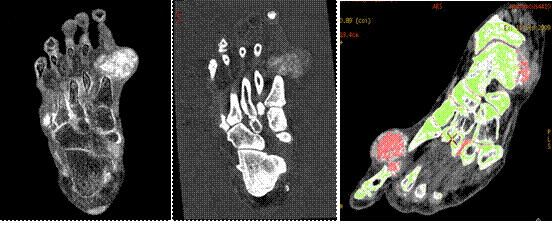

新技术介绍三:物质分离与定量

MD尿酸像 MD钙基像 尿酸与骨质分离

痛风由于尿酸结晶体沉积在人体组织所致,而假性痛风是由于磷酸钙盐沉积所致。如果在关节内不进行穿刺活检无法评估尿酸结晶存在。宝石能谱CT物质分离像可以提示痛风或者假性痛风存在,并加以鉴别。